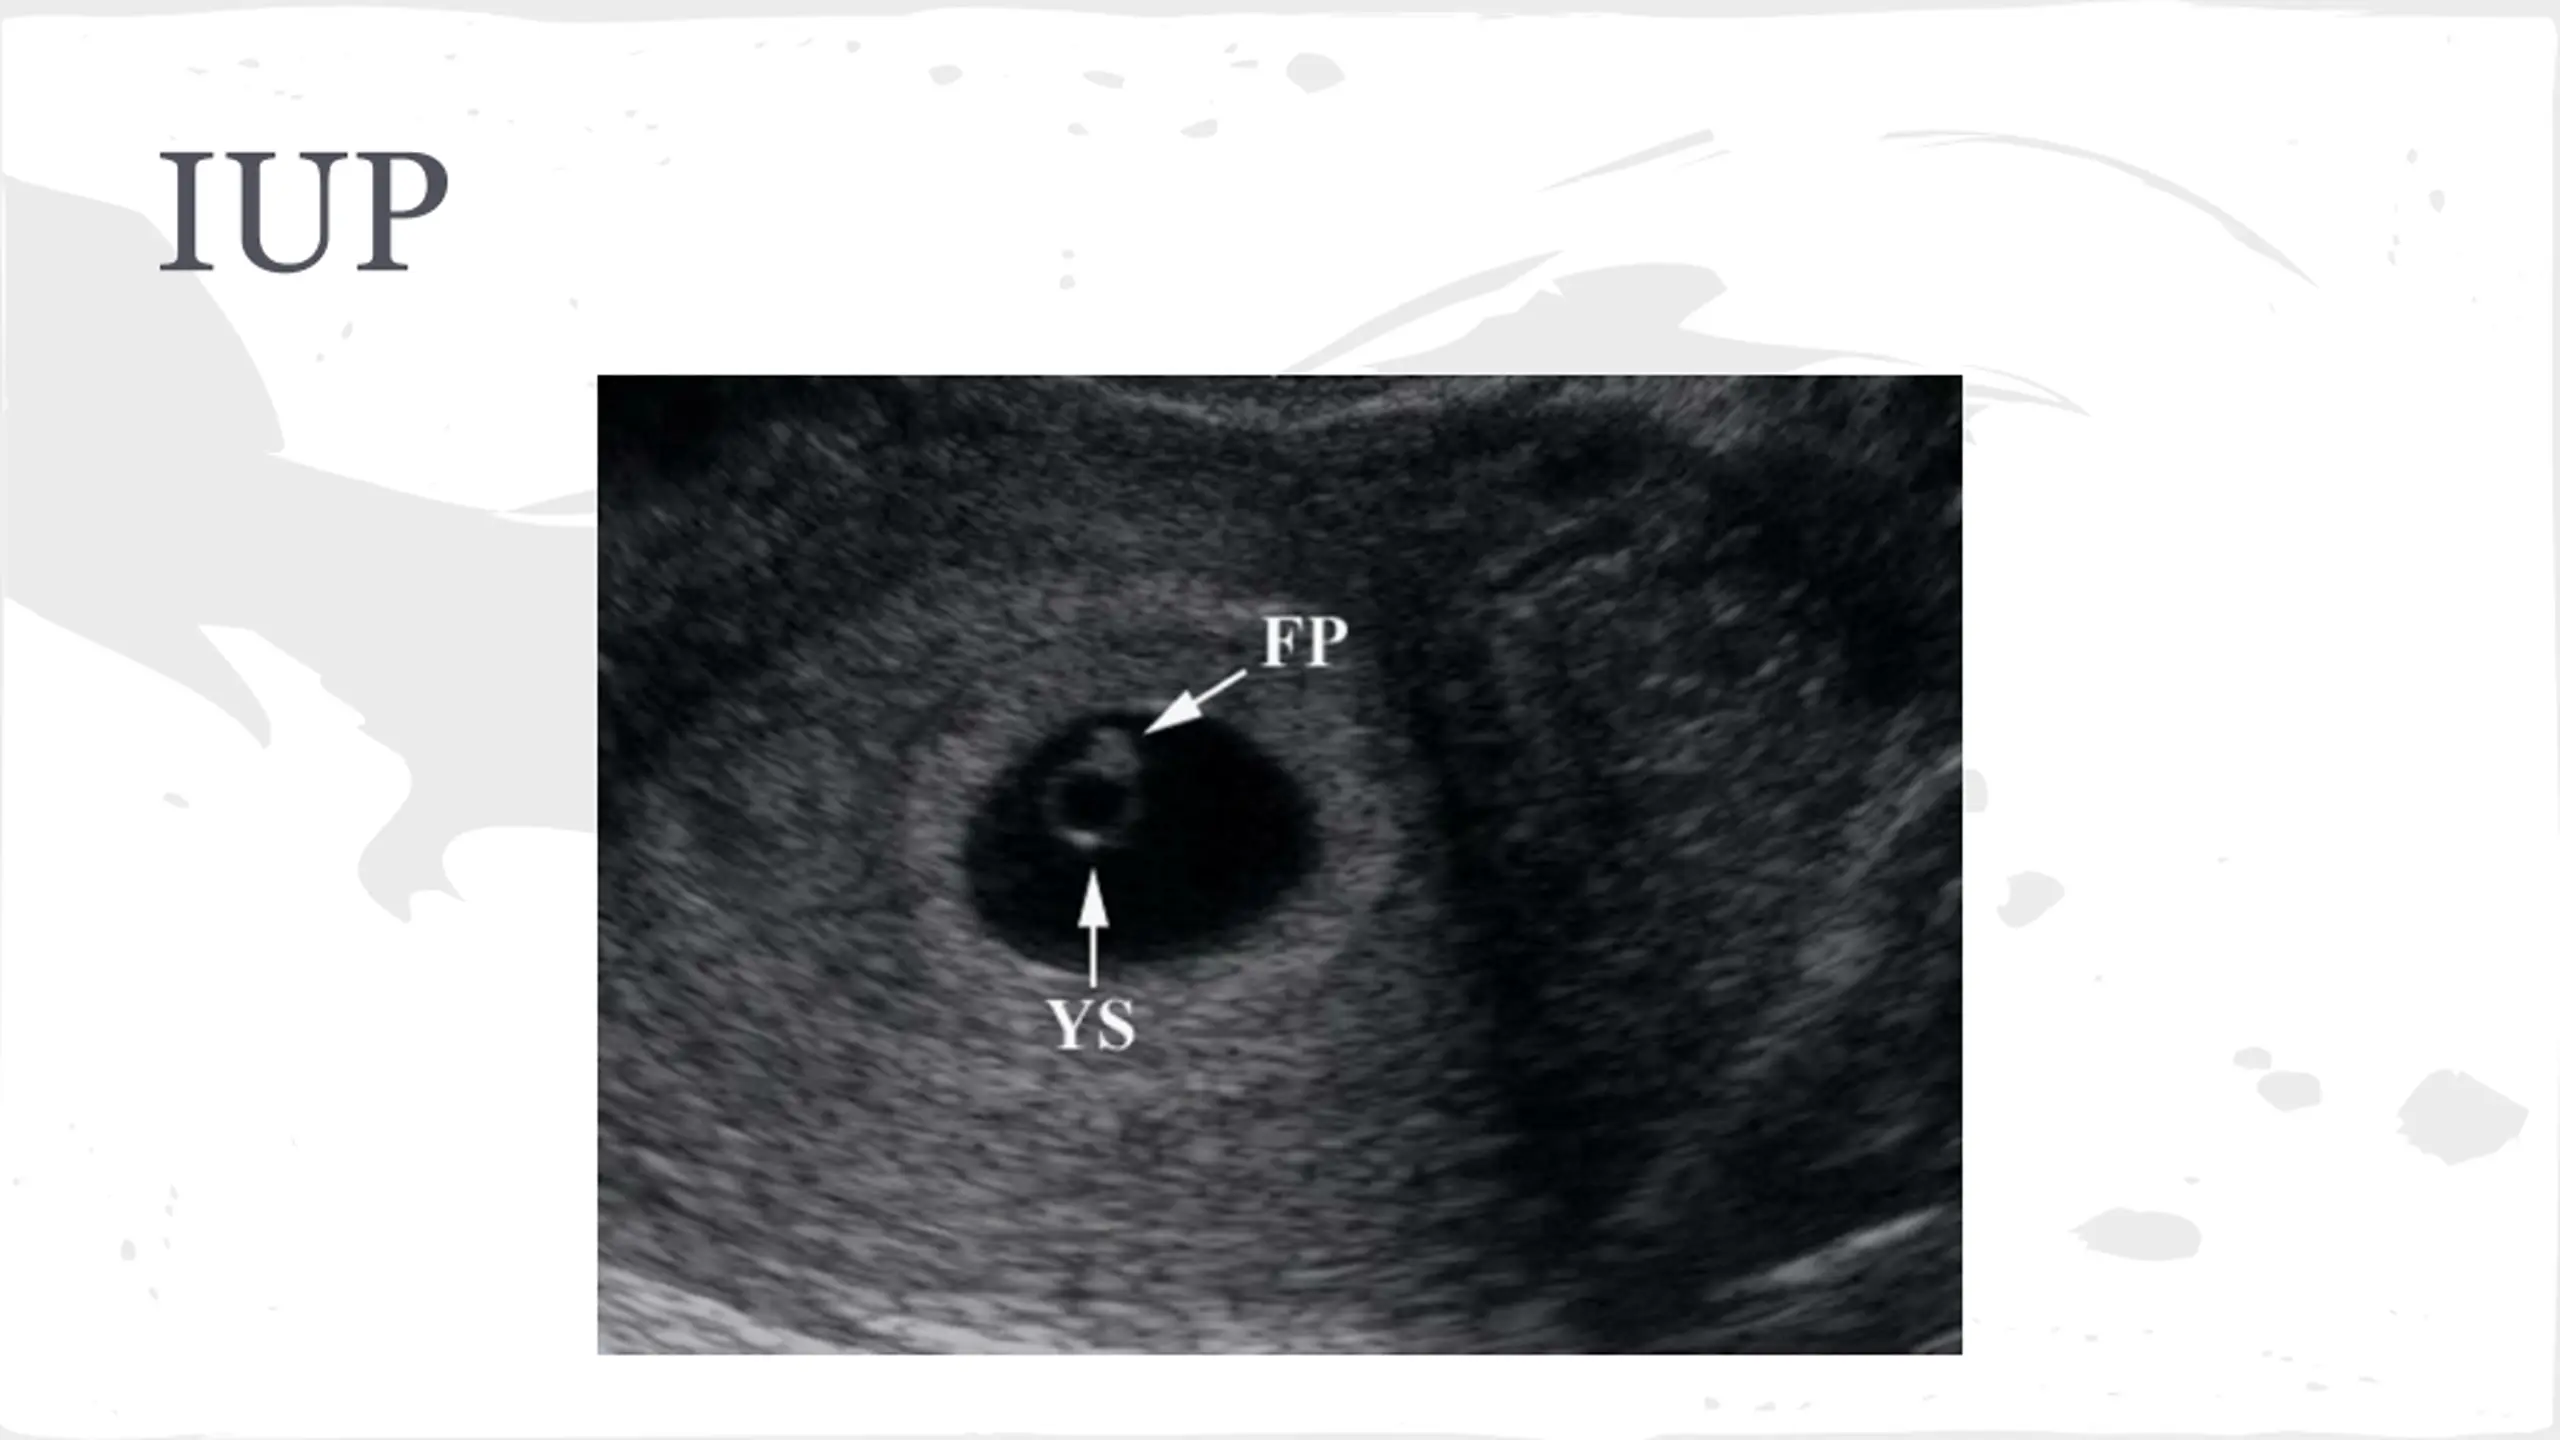

Ectopic Pregnancy-Likelihood Ratios CMT-4.9 Adnexal mass-2.4 Adnexal tenderness 1.9 Ultrasound-111 No IUP on US in pregant patient is ectopic until proven otherwise

Ectopic Pregnancy Symptoms Abdominal Pain Syncope Vaginal Bleeding Vomiting Exam Lower abdominal tenderness Adnexal TTP CMT Peritoneal Abdomen

Ectopic Pregnancy Labs Quant B-HCG, CBC, Coags, Type and Screen -very low B-HCG cannot rule out ectopic Management -STAT GYN consult -NPO -Medical vs Surgical Management